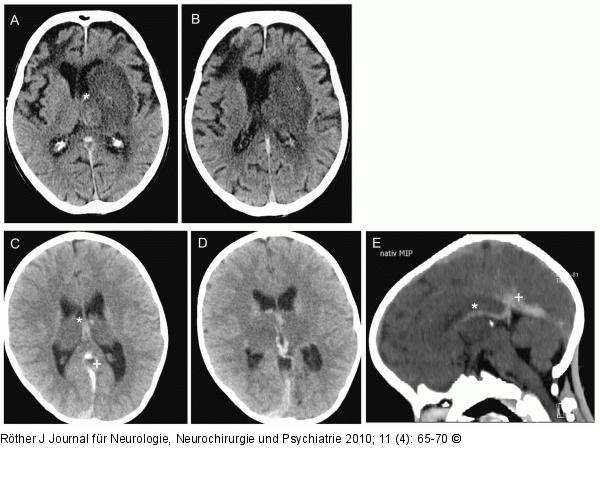

Abbildung 3a-e: SVT A, B: Bildgebung der SVT: Innere Hirnvenenthrombose (*V. thalamostriata) mit Stauungsinfarkt. Hypodensität hält sich nicht an die Grenzen der striatolentikulären Gefäße, sondern umfasst auch den Thalamus! C–E: 6-jähriger Junge mit Down-Syndrom und Colitis. Exsikkose nach Diarrhöen. Innere Hirnvenenthrombose (* V. thalamostriata; + V. Galeni und Sinus rectus). |